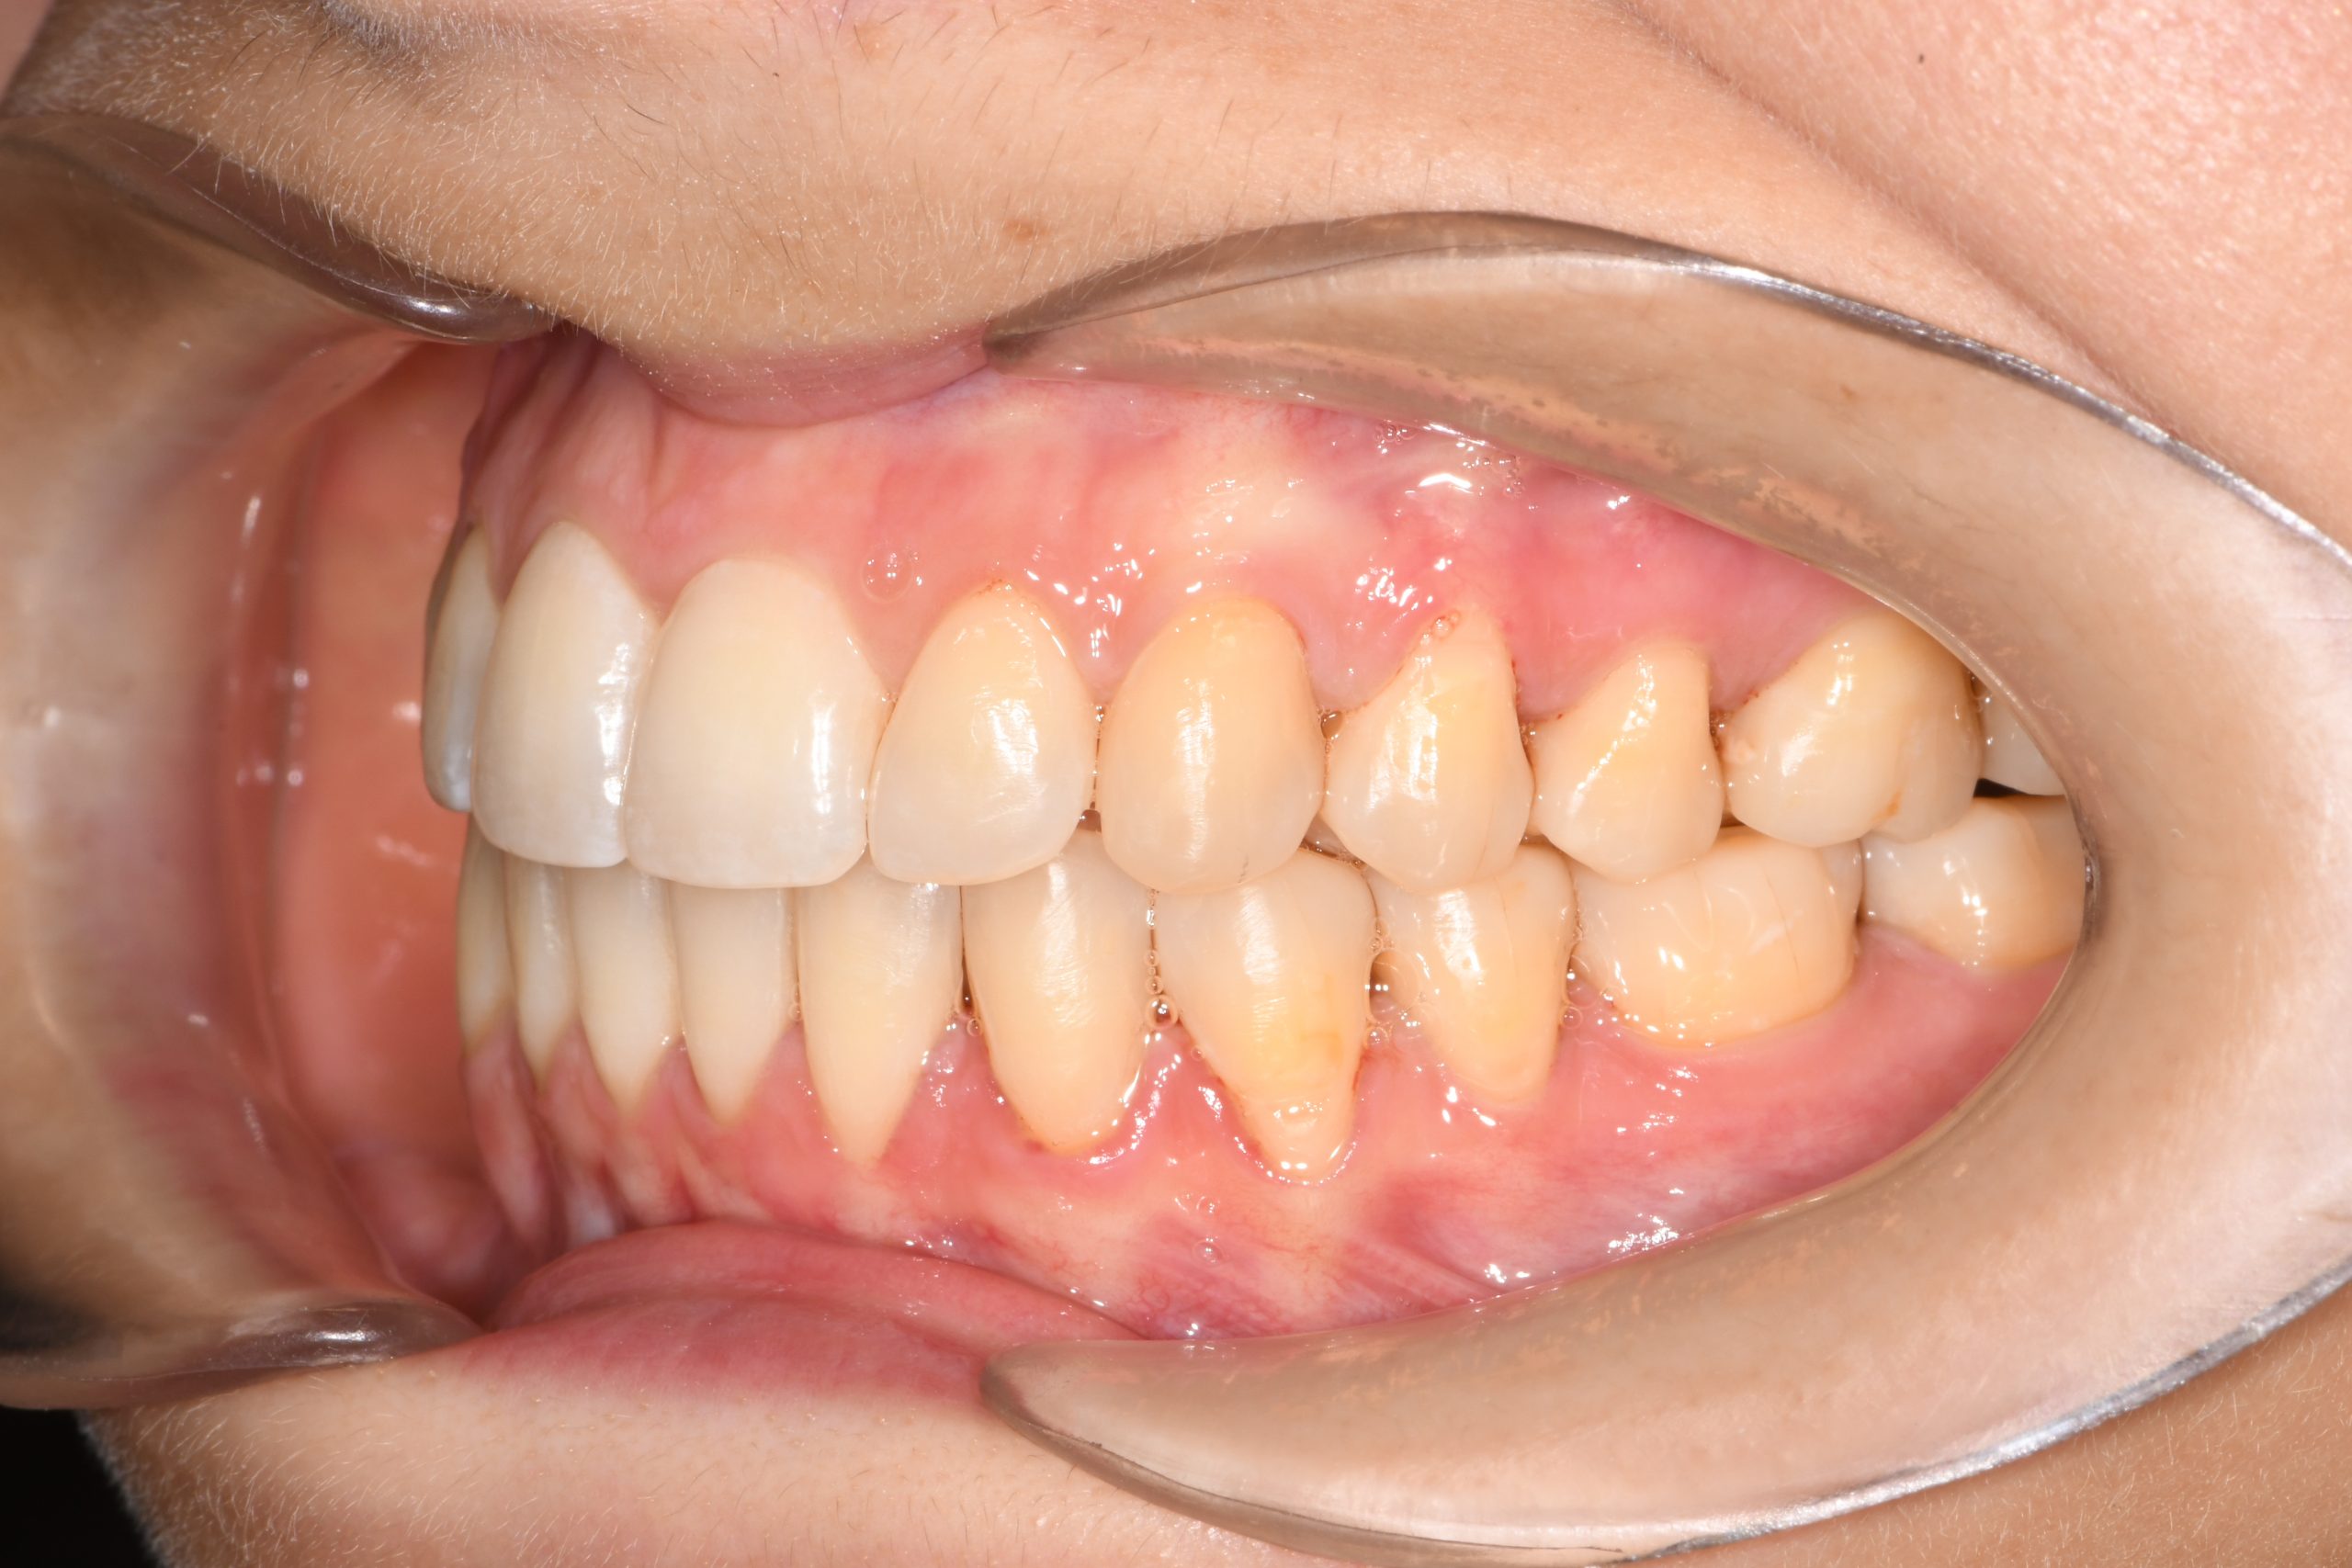

Az elmúlt évekből rengeteg szakmai referenciát tudnánk bemutatni, amelyek különböző fogszabályozási problémákat oldottak meg. Válogatva a több száz esetből, ezen az oldalon olyan képeket, információkat igyekeztünk bemutatni, amelyeknek a segítségével a jövőbeni pácienseinknek azt tudjuk üzenni: A Te fogsorod is lehet gyönyörű!

(Képeket a Pácienseink külön írásos beleegyezésével mutatjuk be!)